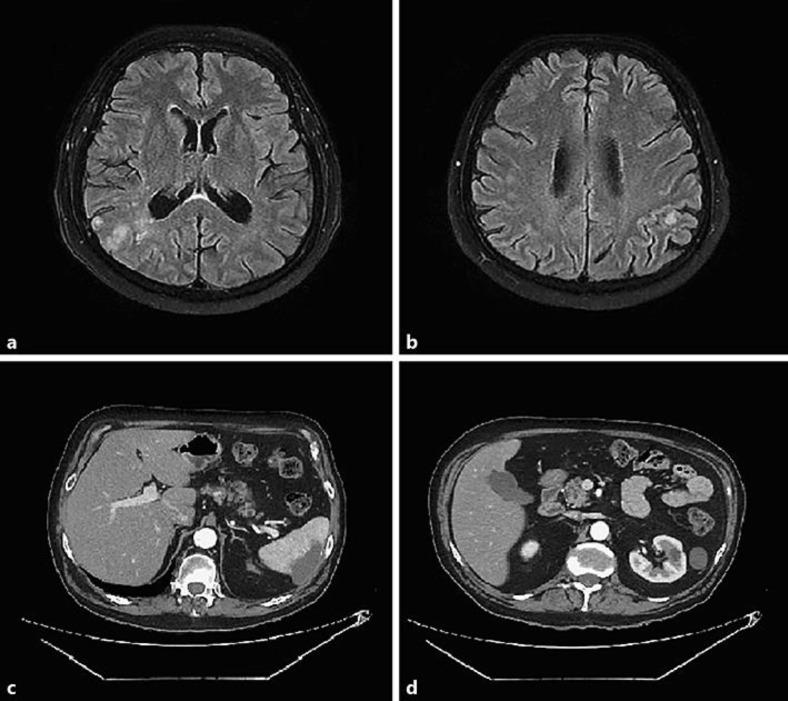

Despite the significant clinical benefits, checkpoint inhibition is associated with a unique spectrum of immune-related adverse events. It is sometimes difficult to distinguish some rare adverse effects from a cancer progression; thus, such effects should be reported in clinical trials to be diagnosed by physicians. Only a few cases of arterial embolic events have been described in studies related to patients treated by immunotherapy. In this article, we report the cases of 2 patients who presented rare and severe thromboembolic events after using checkpoint inhibitors. The first case describes multiple organ embolism at the same time, associated with other autoimmune symptoms. In the second case, distal digital necrosis emerged after the initiation of immunotherapy. There is insufficient data about the real incidence of thromboembolic and rheumatological events related to checkpoint inhibition. Future trials should be done to establish preventive strategies.

尽管具有显著的临床益处,但检查点抑制与一系列独特的免疫相关不良事件有关。有时很难将一些罕见的不良反应与癌症进展区分开来;因此,此类效应应在临床试验中报告,以便医生进行诊断。在与接受免疫治疗的患者相关的研究中,仅描述了少数几例动脉栓塞事件。在本文中,我们报告了2例在使用检查点抑制剂后出现罕见且严重血栓栓塞事件的患者病例。第一例描述了同时发生的多器官栓塞,并伴有其他自身免疫症状。第二例在免疫治疗开始后出现了远端手指坏死。关于与检查点抑制相关的血栓栓塞和风湿性事件的实际发生率的数据不足。未来应开展试验以制定预防策略。